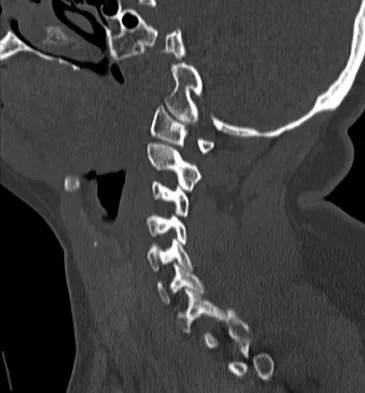

Subluxation caused by rheumatoid arthritis is most commonly seen at what level of the cervical spine?

Explanation

Approximately 65% of cervical subluxations occur at C1-C2. Of these, 50% are anterior, with the remainder being lateral and posterior. The second most common type is basilar invagination, occurring in 40% of patients. The third most common type is subaxial, occurring in 20% of patients with rheumatoid arthritis. Subluxation at more than one level is common. Boden S, Clark CR: Rheumatoid arthritis of the cervical spine, in Clark CR (ed): The Cervical Spine, ed 3. Philadelphia, PA, Lippincott Raven, 1998, p 693. Boden SD, Dodge LD, Bohlman HH, Rechtine GR: Rheumatoid arthritis of the cervical spine: A long-term analysis with predictors of paralysis and recovery. J Bone Joint Surg Am 1993;75:1282-1297.